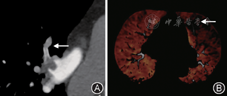

20例患者共40肺动脉(A1)、100叶动脉(A2)、360段动脉(A3)以及755亚段动脉(A4)纳入统计分析范围,CTPA共发现A1 12处、A2 47处、A3 51处、A4 28处内有栓子存在,lung vessels共发现A1 12处、A2 49处、A3 71处及A4 34处内有栓子存在,PED共发现A1 12处、A2 50处、A3 94处及A4 53处内有栓子存在;CTPA、lung vessels及PED对A1、A2、A3以及A4的肺栓塞显示率见(表1,图1)。CTPA、lung vessels及PED对A1以及A2的肺栓塞的显示率差异无统计学意义,CTPA、lung vessels及PED对A3栓塞的显示率两两比较差异均有统计学意义,PED与CTPA、lung vessels对段以下的肺栓塞的显示率差异有统计学意义,而CTPA、lung vessels对段以下的肺栓塞的显示率差异无统计学意义,PED对段以及段以下的肺栓塞的显示率最高,具有最高的临床价值。

20例患者共发现91处肺灌注改变(稀疏或者缺损),其中灌注稀疏64段,灌注缺损27段,以PED图像作为参考标准,以肺段作为评价单位,DEPI图像对肺栓塞的诊断数据见表2,其敏感性为85.7%,特异性为94.1%, kappa系数=0.789,kappa系数≥0.75,说明2种图像对肺栓塞的诊断一致性极好。

本研究发现CTPA、lung vessels及PED对段动脉栓塞的显示率两两比较差异均有统计学意义,PED与CTPA、lung vessels对段以下的肺栓塞的显示率差异有统计学意义,而CTPA、lung vessels对段以下的肺栓塞的显示率差异无统计学意义,PED对段以及段以下的肺栓塞的显示率最高。本研究与相关研究[7,8,9,10]部分一致,但在亚段动脉的肺栓塞发现率存在一定差异[8,9,10]。造成这一差异的主要原因可能与研究病例类型、数目及亚段动脉自身特点有关。Zhang等[9]的研究对象主要为肾病综合征合并肺栓塞的儿童;Krissak等[8]收集病例数目相对较少。且由于全肺段以下的动脉数目巨大,变异较多,给观察带来一定困难,容易产生误差。PED软件弥补这一缺陷,可以逐条检测微小动脉,敏感性高,但易受其他因素影响,特异性低,因此需要医师对可疑栓子进行分析,明确其真实性。

本研究显示DEPI图像对肺栓塞的诊断敏感性为85.7%,特异性为94.1%,敏感性略低,分析原因可能为:(1)本研究收集的病例平均年龄较轻,器官代偿能力较强,当发生肺栓塞时,肺血管可相应增宽,血流灌注变化不大。(2)本研究的对象为微小肺动脉,容易受到多种因素的影响,如引力,造成血流灌注改变不能及时检出。本研究还发现,按照大面积肺栓塞临床诊断标准,大面积肺栓塞共3例,且有大范围的血流灌注异常;而按照影像学诊断标准,共6例,但只有3例发生大范围的血流灌注异常。造成这一结果的原因可能栓子的类型、肺血管的堵塞程度及病人代偿能力有关。张岚等[11]的研究显示肺实质血流动力学的变化与肺栓塞临床表现的严重程度密切相关。因此只有联合PED图像及DEPI图像才能在早期准确诊断肺动脉栓塞并判定严重程度。随着肺动脉栓塞发病率逐渐上升,双源CT在诊断早期肺动脉栓塞及较小动脉栓塞的诊断中发挥了越来越重要作用。